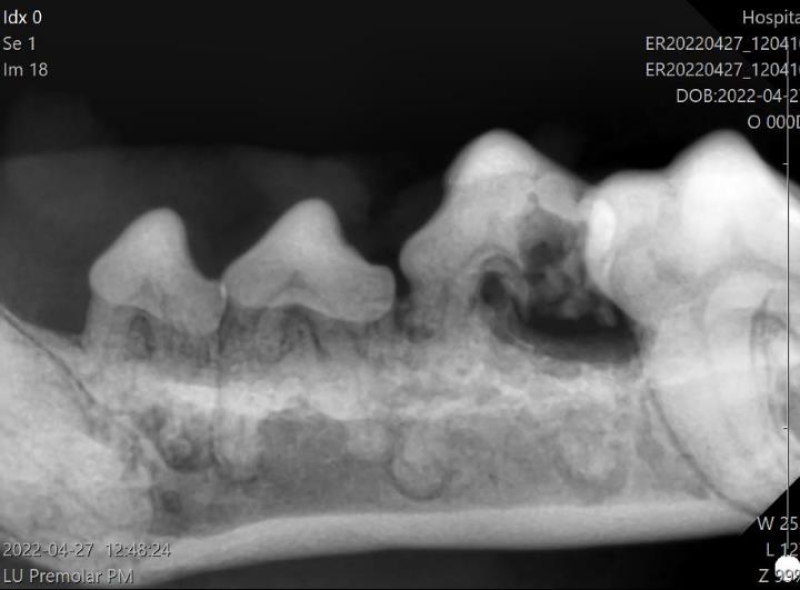

顎骨折(歯周病による下顎骨折)

歯周病や交通事故、衝突などにより、顎の骨を骨折してしまうことがあります。

特に、小型犬種では、顎と歯の大きさが相対的に近くなるため、歯周病が進行した時、下顎骨が吸収(溶けて)骨折することがあります。

治療は、歯周病の治療を行い、病因となっている歯は抜歯し、固定に使えそうな歯または支持組織が残っている場合にはそれを利用して固定を行います。

骨折は、骨折端を合わせて固定することで、約1ヶ月で癒合してきます。

ただし、口は常に動かして使う組織ですので、“固定”が難しく、その治癒が難しいことがあります。